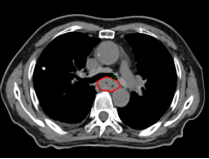

Patient XXX, male, 80 years old, began experiencing difficulty swallowing without obvious cause in February 2022, with progressive worsening. On January 22, 2023, he visited Zhangye People's Hospital, where an upper gastrointestinal contrast study revealed: mid-esophageal stenosis, approximately 5.5 cm in length, with concentric narrowing, mucosal disruption, and irregular filling defects and niches, suggesting mid-esophageal carcinoma (medullary type). On January 25, 2023, gastroscopy at Shanghai XX Hospital showed a circumferential mass protruding into the lumen at 26 cm from the incisors. Pathological examination after biopsy confirmed: (esophageal) squamous cell carcinoma. Upon admission to our hospital, the diagnosis was: 1. Malignant esophageal tumor (mid-esophagus, medullary type, squamous cell carcinoma, cT3N2M0, Stage IVB, KPS score: 90). After multidisciplinary team (MDT) discussion, the treatment plan was determined to be concurrent chemoradiotherapy: 1. Radiotherapy: Photon 40 Gy/20 fractions + carbon ion 16 Gy (RBE)/4 fractions; 2. Chemotherapy: Single-agent oral capecitabine chemotherapy.

Before Photon Radiotherapy Before Carbon Ion Radiotherapy After Carbon Ion Radiotherapy 1 Month After CarboRadiotherapy